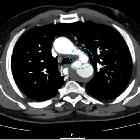

CT

CT, especially with arterial contrast enhancement (CTA) is the investigation of choice, able not only to diagnose and classify the dissection but also to evaluate for distal complications. It has reported sensitivity and specificity of nearly 100% .

Non-contrast CT may demonstrate only subtle findings; however, a high-density mural haematoma is often visible. Displacement of atherosclerotic calcification into the lumen is also a frequently identified finding.

Dissections involving the aortic root should ideally be assessed with ECG-gated CTA which nearly totally eliminates pulsation artefact. Pulsation artefact can mimic dissection, is very common and seen in up to 92% of non-gated CTA studies .

Contrast-enhanced CT (preferably CTA) gives excellent detail. Findings include :

- intimal flap

- double-lumen

- dilatation of the aorta

- complications (see below)

- an atypical variant that may be seen is an aortic intramural haematoma

- Mercedes-Benz sign in the case of a "triple-barreled" dissection

- windsock sign